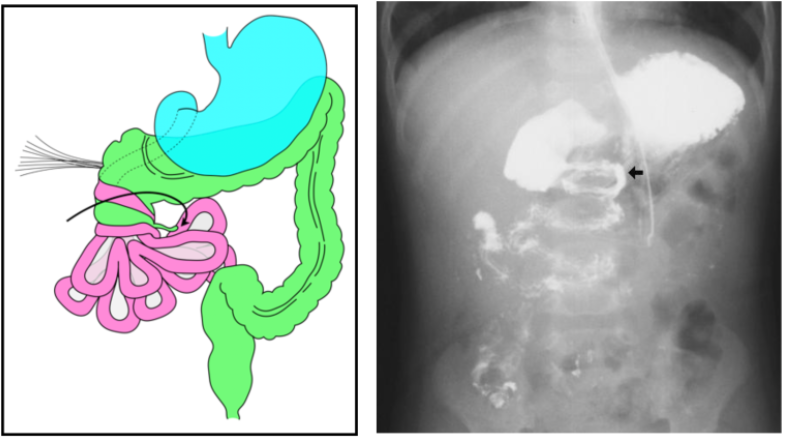

Midgut malrotation